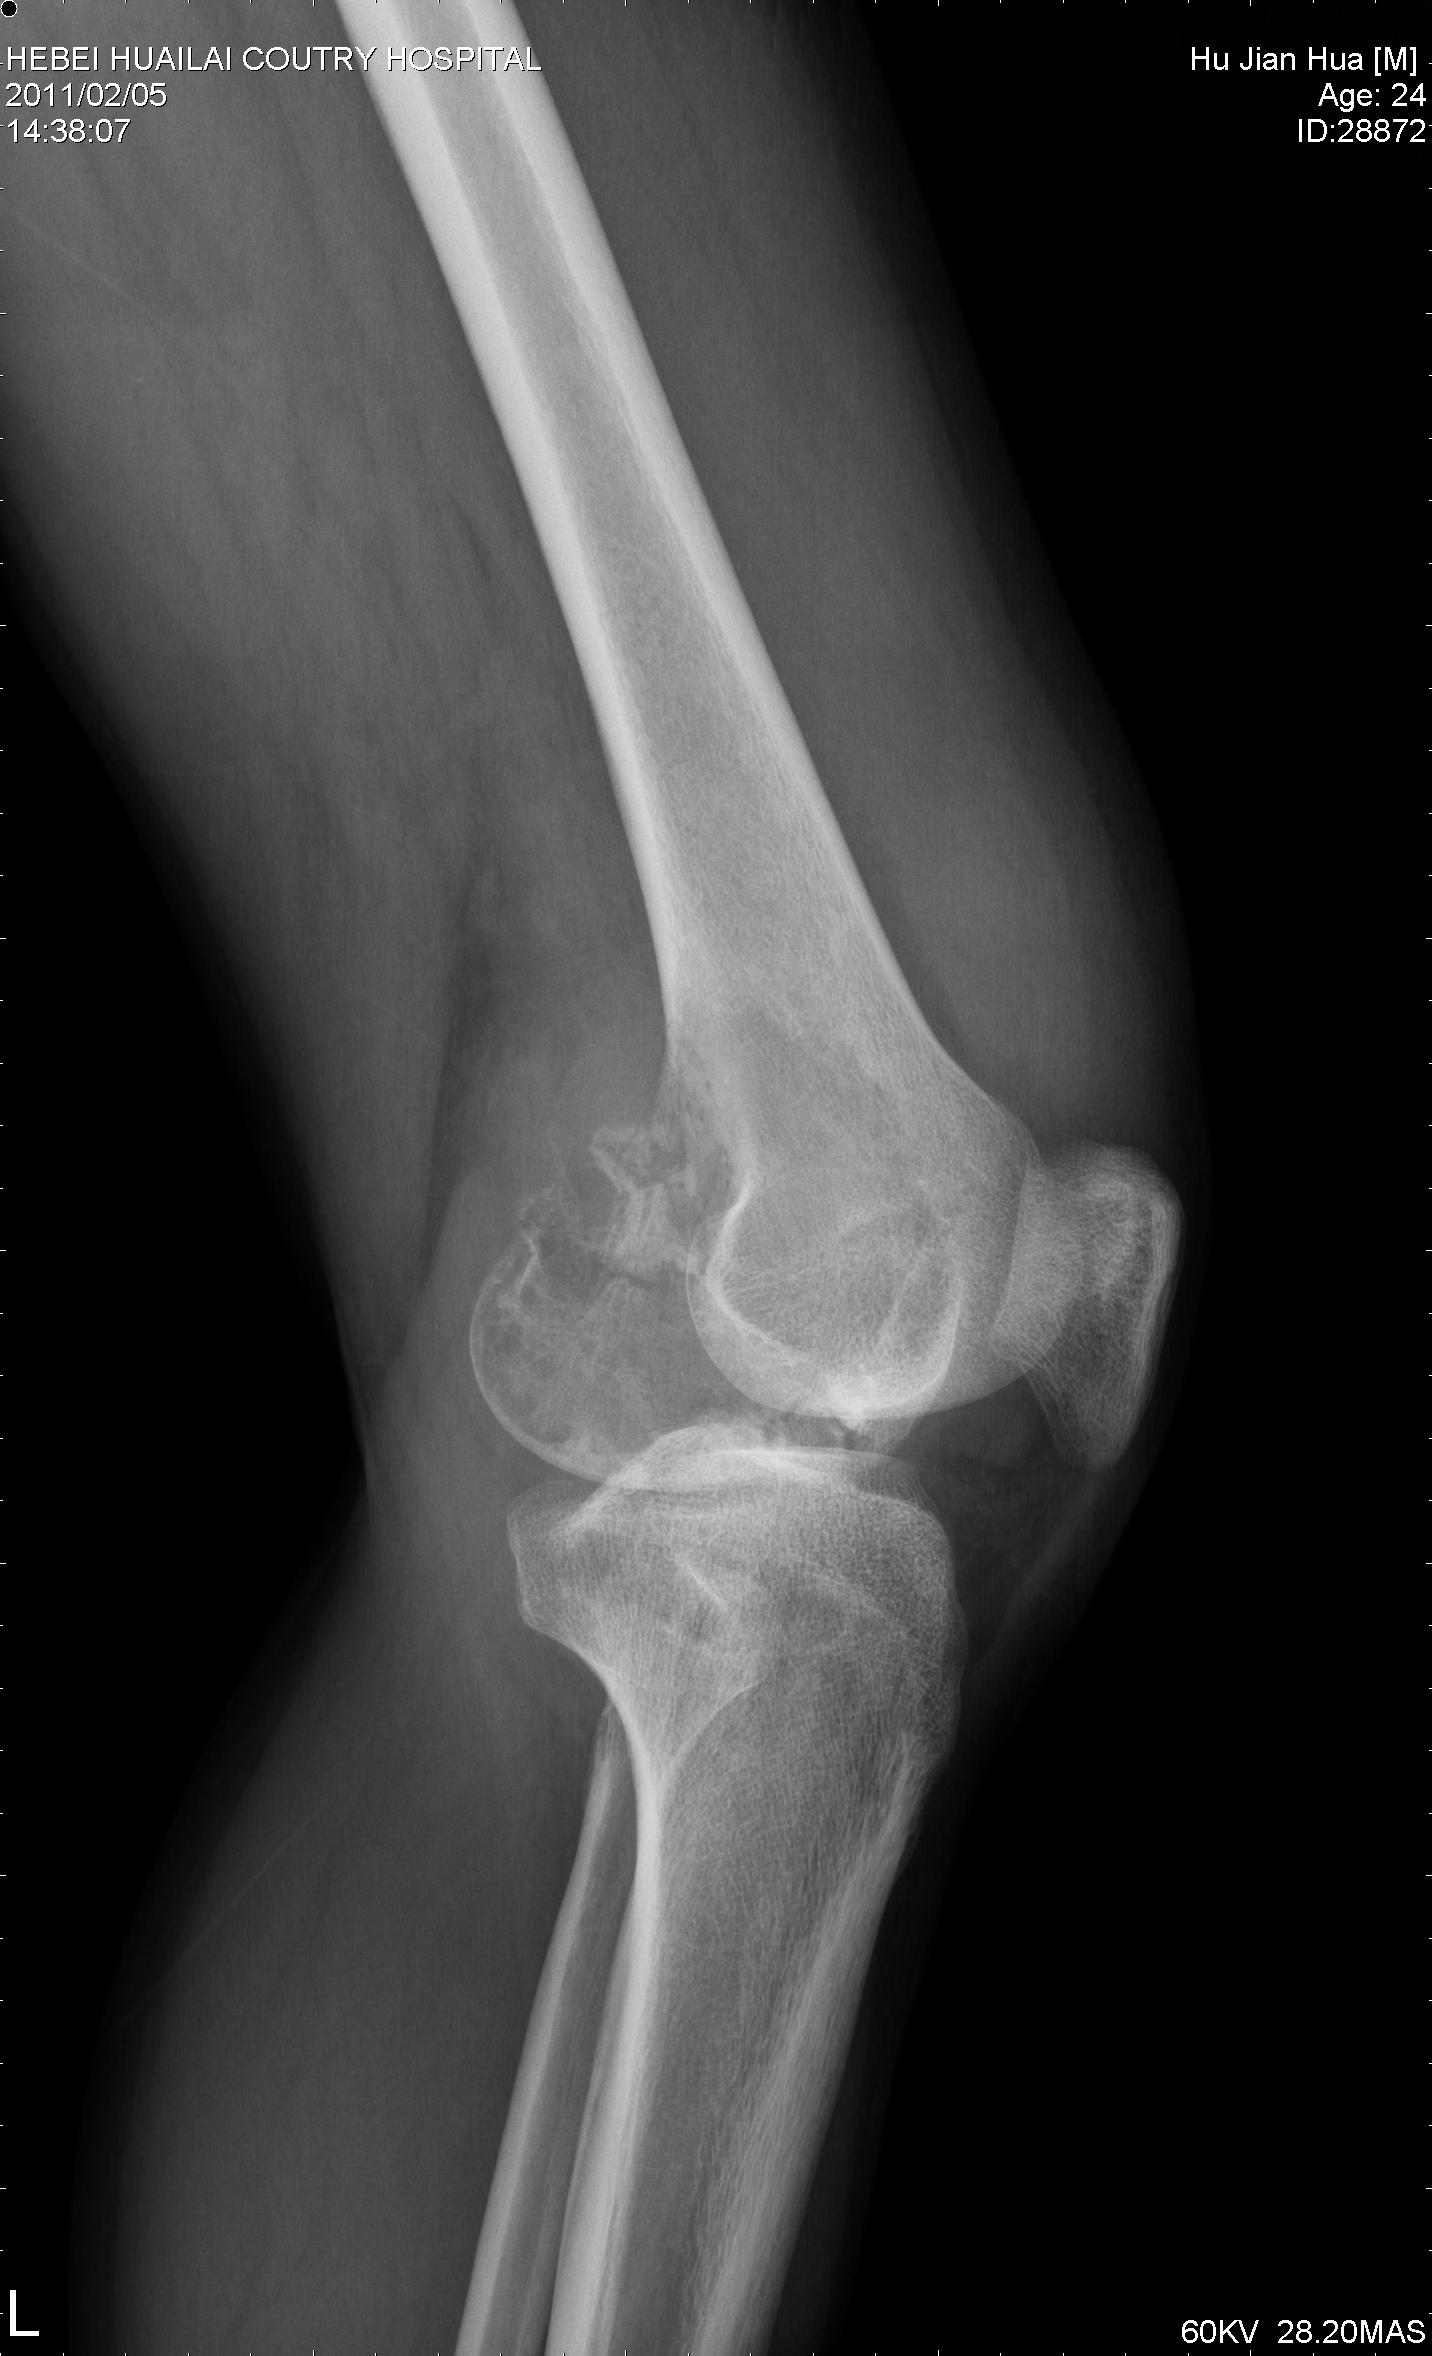

骨巨细胞瘤

患者24岁,左膝疼痛半年余就诊,拟诊左股骨远骨肉瘤,请各位同仁不吝赐教

病例结果:病人已在301医院接受膝关节置换手术,病理结果为